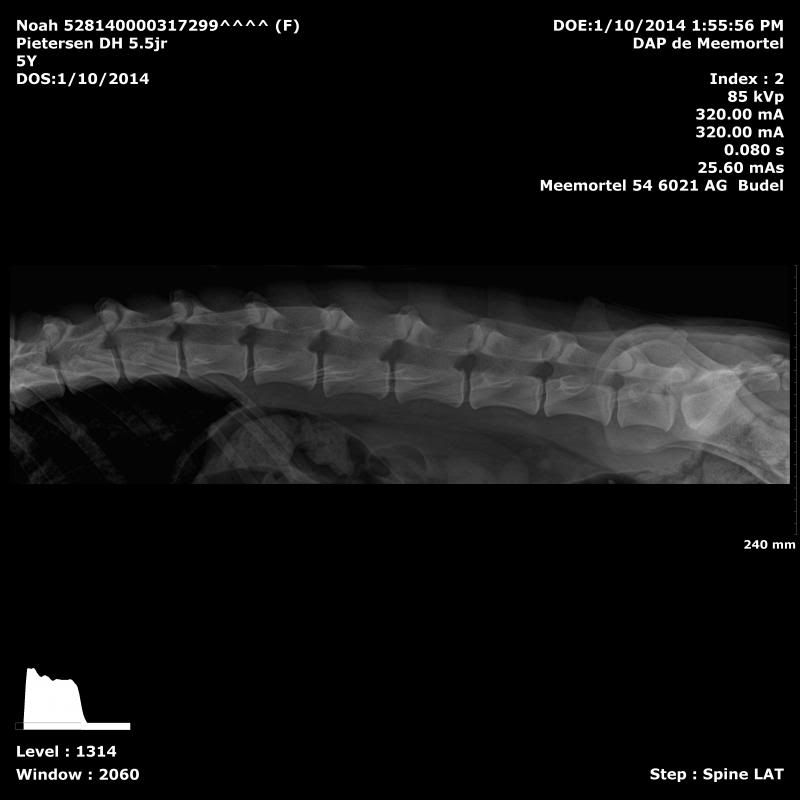

Omdat ik haar behoorlijk veel belast, wil ik graag weten wat de stand van zaken is. Aangezien het nu nog steeds perfect is, ga ik haar ook niet meer doen tenzij er aanleiding naar is. Je hoort zoveel horror verhalen dat ik haar eigenlijk elke 2 jaar wilde doen. Maar dat is gelukkig niet nodig, goed blijft goedLongFields schreef:Zeker goed en positief nieuws! En gelukkig is zij niet de enige rashond waarbij de gezondheid/gewrichten gewoon goed zijn én blijven, ondanks belasting.

Even een nieuwsgierige vraag, waarom heb je haar nu inmiddels 3x laten röntgenen?